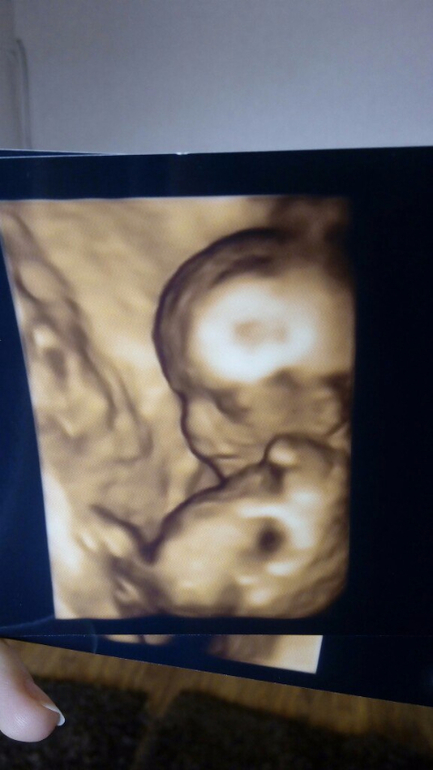

0:30- выложу фото пуза на ББ в альбом, пусть хранится тут, чтоб не потерялся.

А вот и фоточки к рассказу, кто читал, тот поймет))